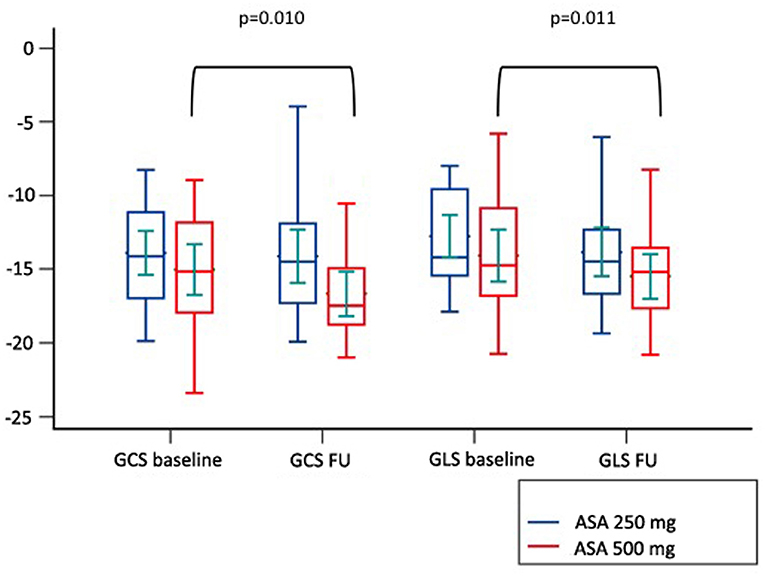

Among cardiovascular drugs administered before PCI, patients with LV adverse remodeling were less frequently treated with ASA loading dose (500 mg), compared to those with reverse or null remodeling (Table 1). Thus, we decided to assess the ASA loading dose effect according to LV remodeling groups. Among the 45 STEMI patients who received a traceable dose of ASA before PCI, 22 STEMI underwent to ASA loading dose, and 23 patients to ASA 250 mg. No differences according to demographic and clinical variables between the two groups were found (Table 3). Patients receiving ASA loading dose before PCI had lower MVO and lower IS extent at baseline and FU-CMR and better strain values (GRS and GCS) compared to those treated with ASA 250 mg (Table 4). Moreover, in the ASA loading group a significant improvement of GCS and GLS, but not GRS values, between baseline and FU-CMR exams (GCS −15.09 ± 3.8 to −16.7 ± 3.2%, p = 0.010, GLS −14.1 ± 3.9 to −15.7 ± 3.2%, p = 0.011, GRS 31.0 ± 7.8 to 32.9 ± 7%, p = 0.104) was noted. Meanwhile, no significant differences of GCS and GLS values between two paired CMR exams within the group treated with lower ASA doses (GCS −13.8 ± 3.5 to −14.1 ± 3.9% p = 0.612, GLS −12.9 ± 3.3 to −13.8 ± 3.7%, p = 0.232, GRS 28.2 ± 6.6 to 27.4 ± 7.9%, p = 0.594) were observed (Figure 4).

Figure 4. Comparison of paired GLS and GCS values between CMR at baseline and at follow up according to pre-pPCI ASA loading dose. GCS, global circumferential strain; GLS, global longitudinal strain; ASA, aspirin.